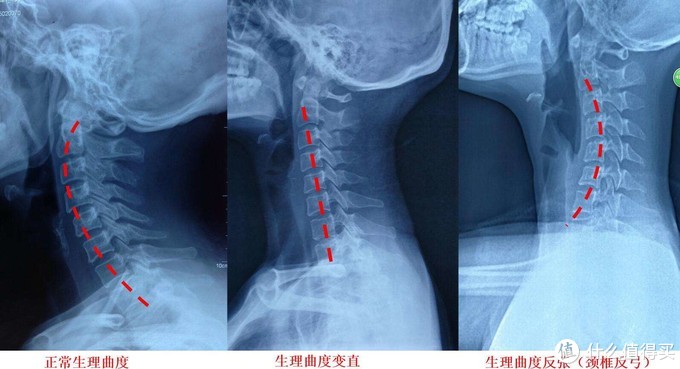

在医学上来说,颈椎指的是我们人体脊椎的第1~7节椎骨,并且包括了穿过其中的脊神经,以及颈椎周围的颈椎肌群。颈椎系统与我们的头部以及胸椎相连,如果只是承托头部而忽视了对颈部及肩部的承托,那么颈椎就会呈现反曲压迫,是的颈椎肌群不能得到放松和修复,久而久之就会形成病理性的颈椎强直,并引发各种颈椎病及衍生病症。而如果只承托颈部,而忽视了对头部及肩部的承托,那么就会导致颈椎过曲,照样会引发问题。